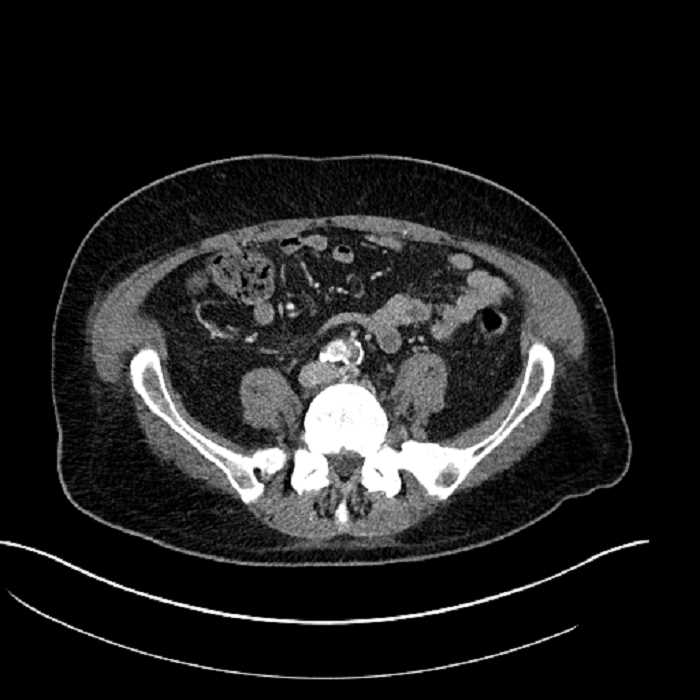

• Mild mural thickening of a segment of the sigmoid colon with adjacent fat stranding and a 1.5 cm fluid and gas collection along the tip of an inflamed diverticulum

• Loss of the normal fat plane between this collection and adjacent loops of small bowel, which demonstrate mural thickening

• No bowel obstruction

• High grade stenosis of the left common iliac artery, with the left internal and external iliac arteries remaining patent

Acute sigmoid diverticulitis complicated by a small contained perforation and a large abscess in the right hepatic lobe. Additional small subcapsular abscesses along the anterior margin of the left hepatic lobe.

Additionally, loss of the normal fat plane between the peridiverticular collection and adjacent thickened loops of small bowel raises the potential for an enterocolonic fistula.

High grade stenosis of the left common iliac artery. The left external and internal iliac arteries are patent.

Hepatic abscess showing the double target sign with low density internally surrounded by a thin inner enhancing rim (red arrow) and ill-defined outer low density rim (yellow arrow). Blue arrow indicates an internal septation. Red arrows: additional smaller subcapsular abscesses. Red arrow: focal contained perforation associated with diverticulitis.